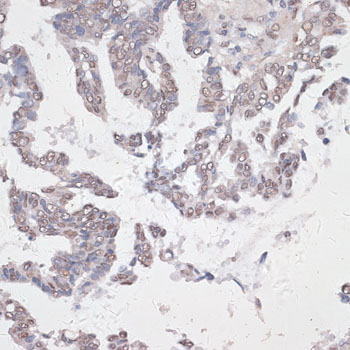

Immunohistochemistry of paraffin-embedded human lung cancer using CREB1 antibody.